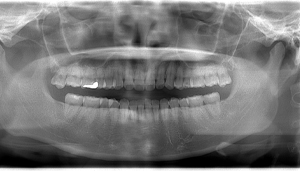

右上の親知らず抜歯症例

- 抜歯前写真(レントゲン)

- 抜去歯の写真

| 年齢 | 40代・男性 |

|---|---|

| 主訴 | 右上8番抜歯したい |

| 治療期間 | 1日 |

| 費用 | 2,620円 (2022年12月現在) |

| 担当者所見 | レントゲンでは上顎洞に親知らずが突き刺さっているように見えましたが、抜歯後穿通は見られませんでした。 抜歯後2、3日をピークに腫れ、発熱、内出血が出ることがありますが、痛み止めを飲んでしのげる程度がほとんどです。 抜歯後は細菌感染のリスクがあるため抜いたところを舌や指で刺激しないよう注意してもらいます。 |

| リスク・副作用 | 抜歯の際、上顎洞に穴が空くことがありますが、空いた穴が小さく炎症を起こさなければ自然に塞がります。 抜歯後2,3日が腫れのピークになり発熱、内出血が出ることがありますが、痛み止めを飲んでしのげる場合がほとんどです。 抜歯後は細菌感染のリスクがあるため抜いたところを舌や指で刺激しないように注意してもらいます。 激しくゆすぎすぎるとドライソケットになるため、うがいは優しくするようにしてもらいます。 |